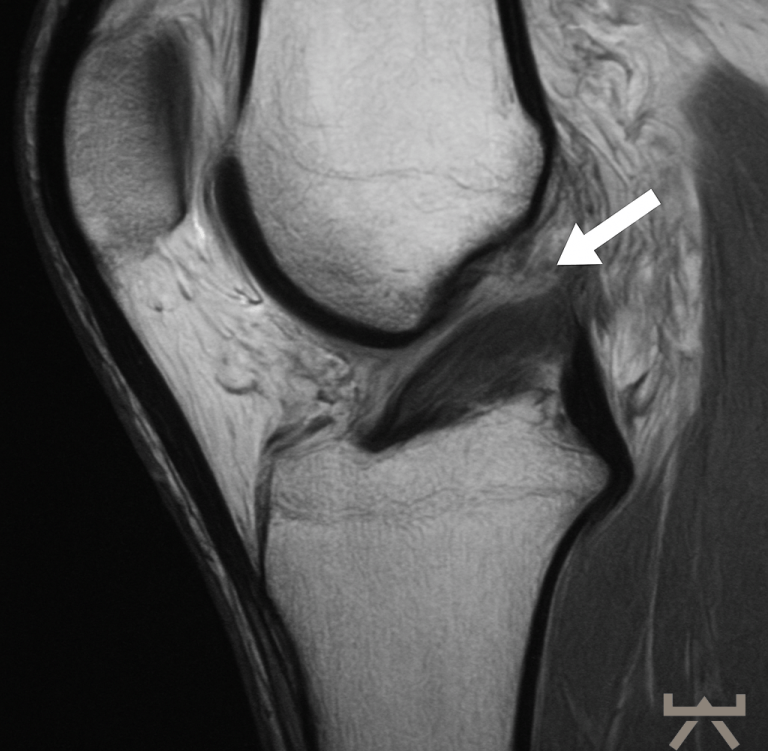

Starke Schmerzen und dadurch eine hohe Muskelspannung können die Durchführung und somit auch die Beurteilung der Tests erschweren. Daher können bildgebende diagnostische Mittel hier eine Alternative sein:

- MRT

- CT

Durch die Schwellung ist die Diagnostik in der Bildgebung jedoch erschwert, daher muss diese nach dem Trauma schnellstmöglich erfolgen oder es kann eine wiederholte Untersuchung in der subakuten Phase sinnvoll sein. Hierfür eignen sich die oben aufgelisteten bildgebenden diagnostischen Mittel, wobei das MRT hier die erste Wahl ist. In diesen Untersuchungen werden die nötigen Strukturen des Knies dargestellt. Auch häufige Begleitverletzungen wie Meniskusschäden oder Verletzungen des Außenbandes können in der Magnetresonanztomographie direkt ausgeschlossen/diagnostiziert werden.

Trotzdem muss man berücksichtigen, dass bildhafte Verfahren zur Diagnostik mit Vorsicht zu genießen sind. So müssen nicht alle degenerative bzw. schadhaften Veränderungen von Bedeutung sein, da sie auch normale Alterungsprozesse des Lebens abbilden können. Sowie sich unser Äußeres im Alter verändert (z.B. Falten), verändern sich auch unsere inneren Strukturen im Laufe des Lebens.